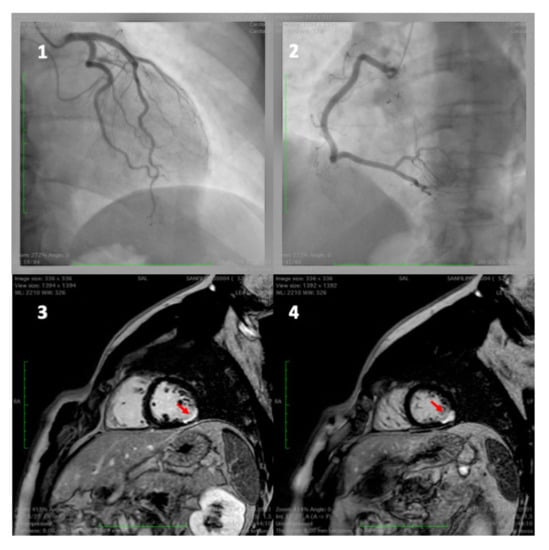

- Yeung, A.C.; Vekshtein, V.I.; Krantz, D.S.; Vita, J.A.; Ryan, T.J., Jr.; Ganz, P.; Selwyn, A.P. The Effect of Atherosclerosis on the Vasomotor Response of Coronary Arteries to Mental Stress. N. Engl. J. Med. 1991, 325, 1551–1556. [Google Scholar] [CrossRef]

- Kop, W.J.; Krantz, D.S.; Howell, R.H.; Ferguson, M.A.; Papademetriou, V.; Lu, D.; Popma, J.J.; Quigley, J.F.; Vernalis, M.; Gottdiener, J.S. Effects of Mental stress on Coronary epicardial vasomotion and flow velocity in Coronary artery disease: Relationship with hemodynamic stress responses. J. Am. Coll. Cardiol. 2001, 37, 1359–1366. [Google Scholar] [CrossRef]

- Arrighi, J.A.; Burg, M.; Cohen, I.S.; Kao, A.H.; Pfau, S.; Caulin-Glaser, T.; Zaret, B.L.; Soufer, R. Myocardial blood-flow response during mental stress in patients with coronary artery disease. Lancet 2000, 356, 310–311. [Google Scholar] [CrossRef]

- Dakak, N.; Quyyumi, A.A.; Eisenhofer, G.; Goldstein, D.S.; Cannon, R.O. Sympathetically mediated effects of mental stress on the cardiac microcirculation of patients with coronary artery disease. Am. J. Cardiol. 1995, 76, 125–130. [Google Scholar] [CrossRef]

- Ma, H.; Guo, L.; Huang, D.; Wang, L.; Guo, L.; Geng, Q.; Zhang, M. The Role of the Myocardial Microvasculature in Mental Stress-Induced Myocardial Ischemia. Clin. Cardiol. 2016, 39, 234–239. [Google Scholar] [CrossRef] [PubMed]